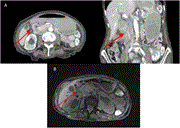

Radio-pathological diagnosis of a retroperitoneal cavernous hemangioma

Ahmed S Khazaal and others

Journal of Surgical Case Reports, Volume 2023, Issue 3, March 2023, rjad095, https://doi.org/10.1093/jscr/rjad095